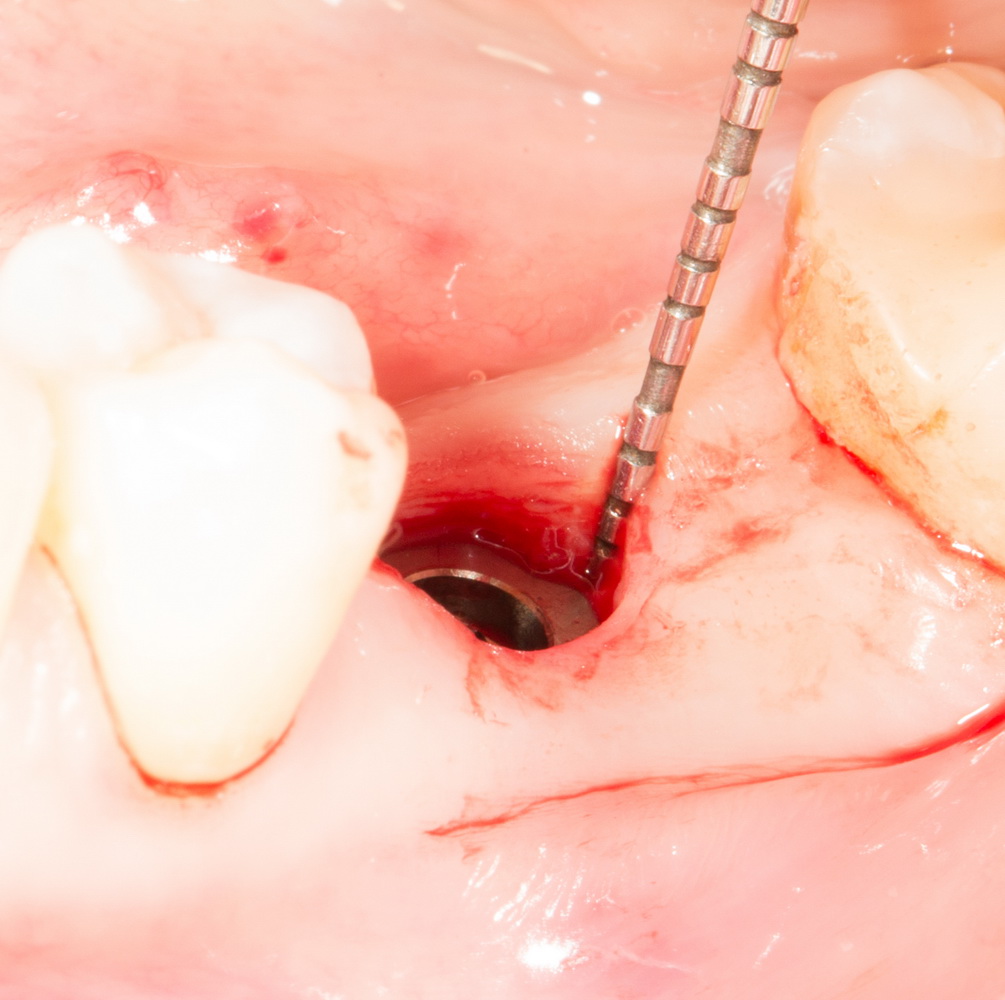

Дальнейшая подготовка лунки идет через образовавшееся отверстие:

С помощью последовательного набора фрез, лунка расширяется и углубляется под имплантат нужного диаметра. Тут важно знать толщину слизистой оболочки (измеряется зондом в самом начале) и делать поправку по глубине. Скажем, нужно поставить имплантат длиной 11 мм, толщина десны по пародонтологическому зонду — 3 мм. Следовательно, фреза погружается до отметки 14-15 мм.

Контроль глубины в данном случае затруднен и поэтому очень важен. За исключением некоторых видов трансгингивальных и субкрестальных имплантов, наш «корень зуба» должен оказаться на определенной глубине, его полированная фаска и ортопедический интерфейс должны быть выше уровня десны. Если при обычном линейном разрезе мы видим костную ткань и это облегчает ориентирование по глубине, то в данном случае ориентиров почти нет.